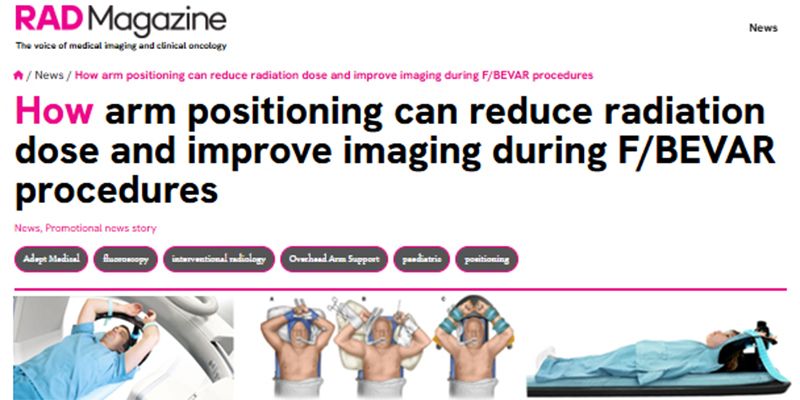

We design medical devices that support patient positioning, clinician ergonomics and procedural workflow in interventional radiology, cardiology and neuroradiology. Devices also available for otology, rhinology and sterilisation.

Interventional RadiologyInterventional CardiologyInterventional NeuroradiologyPeripheral InterventionGeneral Surgical

Since 2003, we’ve been designing and manufacturing purpose-built medical devices that support clinicians, simplify workflow, and enhance patient care.

We focus on quality, performance and reliability to help support better outcomes for both patients and healthcare professionals. Our design engineers interact early with clinicians to ensure our products integrate seamlessly with existing workflows.